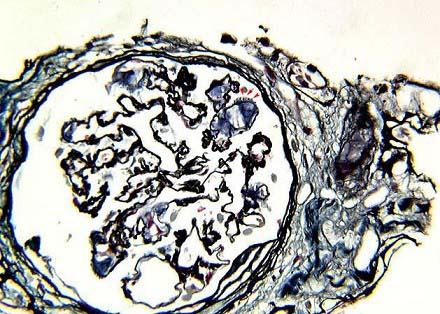

问题 PASM染色基底膜有不规则的羽毛状物质沉积,偏光显微镜下有绿色表现,电镜以淀粉样纤维沉积为特点,其病理诊断可考虑为 ( )

选项 A.糖尿病肾病 B.高血压肾损害 C.肾淀粉样变性 D.乙肝相关性肾炎 E.肾小球肾炎

答案 C